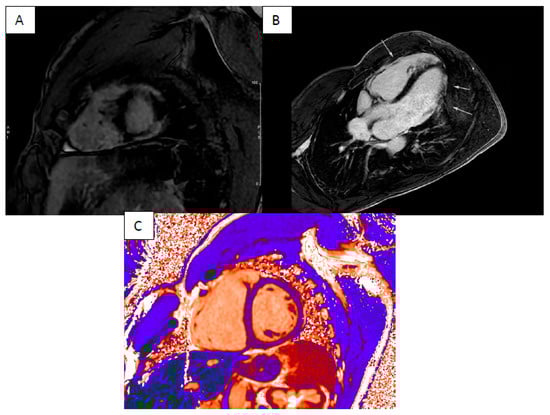

3. Cardiac Sarcoidosis